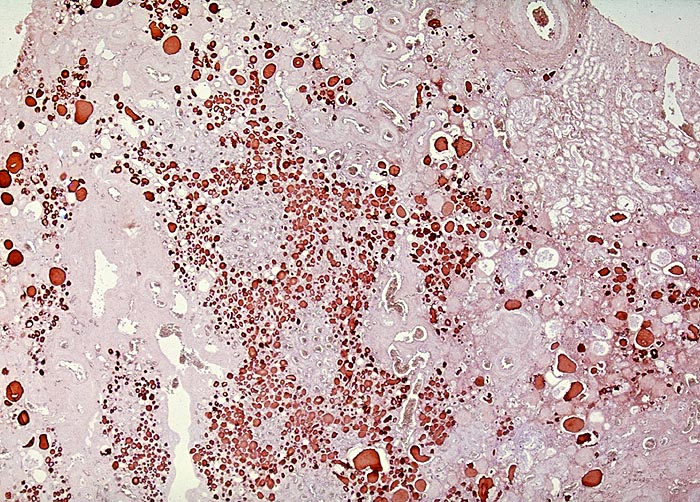

Pseudostrumaherd

Pseudostrumaherd mit dilatierten Tubuli gefüllt mit Harnmukoid. Die Harnmukoidzylinder enthalten massenhaft IgA.

Inkubation mit Tamm-Horsfall Protein Antikörper zeigte ein identisches Bild.

Chronische Pyelonephritis: neben unverändertem Parenchym herdförmige lymphoplasmohistiozytäre Infiltrate (bei akutem Schub zusäztlich neutrophile Granulozyten). Granulationsgewebe im Interstitium führt schliesslich zur Narbenbildung und Nierenschrumpfung.

Pseudostrumabild: Gruppen erhaltener dilatierter Tubuli mit abgeflachtem Epithel enthalten sogenanntes Harnmukoid (Tamm-Horsfall Protein und/oder IgA). Bei kindlicher Pyelonephritis häufig auch Lymphfollikel. Pseudostrumaherde sind ein wichtiger Hinweis, aber kein Beweis für chronische Pyelonephritis.